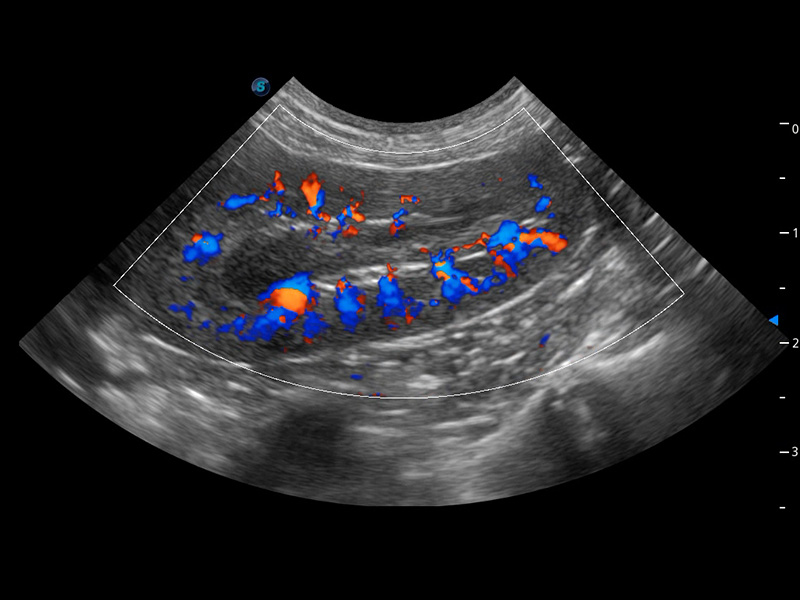

ProPet 60 作为一款高端台式动物超声设备,为动物医生的日常诊断提供了一系列贴合动物临床需求、解决临床实际问题的高级成像功能。凭借全系列高清探头,满足医生对腹部、心脏、生殖、浅表、肌骨等成像的所有需求,切实帮助您提升检查效率,提高诊断信心。

动物是人类最亲密的朋友和最值得信赖的伙伴。银河集团官网也一直致力于探索动物专用的超声影像解决方案。 全新推出的ProPet系列,是银河集团官网在动物超声影像智能化、专业化、精准化的一次跨越式革新。动物不能用言语来表述自己的不适,通过超声影像,ProPet系列搭建了动物医生与不同物种沟通的“桥梁”,为动物医生注入了“治愈之力”。